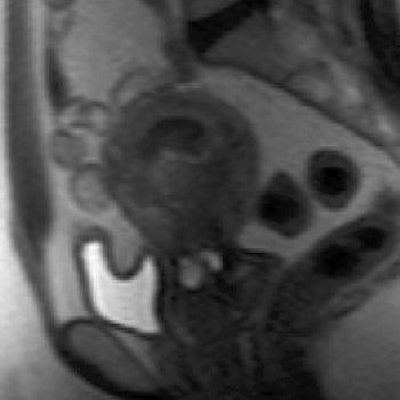

![]() |

| Same patient. Above, T2-weighted sagittal image obtained four months after treatment shows decrease in uterine size and junctional zone thickness, and new area of decreased signal intensity in region of adenomyosis. Below, contrast-enhanced T1-weighted sagittal image obtained during same study shows nonenhancement of this area, which signified devascularization in region of adenomyosis. Kitamura Y, Allison SJ, Jha RC, Spies JB, Flick PA, Ascher SM, "MRI of Adenomyosis: Changes with Uterine Artery Embolization" (AJR 2006; 186:855-864). |